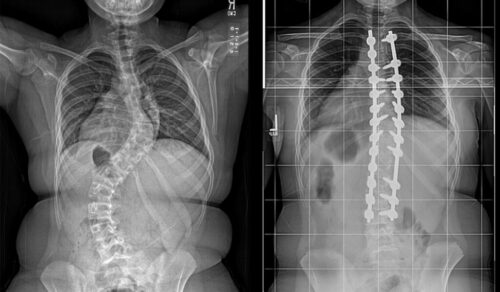

يبدأ هذا النوع منذ مرحلة الطفولة أو المراهقة ويستمر حتى البلوغ. بعد اكتمال نمو العظام، قد يتوقف تطور الانحناء، لكن مع تقدم العمر، يمكن أن يزداد الانحناء نتيجة تدهور الأقراص والغضاريف بين الفقرات. يعرف هذا النوع أحيانًا باسم الجنف التنكسي عند البالغين.الجنف التنكسي الجديد (De-Novo Scoliosis)

يظهر هذا النوع لأول مرة عند البالغين دون تاريخ سابق للجنف. يحدث غالبًا بسبب تآكل الغضاريف والمفاصل بين الفقرات، خاصة في المنطقة القطنية. في بعض الحالات، يصعب التمييز بينه وبين النوع الأول، خصوصًا إذا لم يتم تشخيص الانحناء في سن مبكرة.

خطط علاجية مخصصة: نوفر برامج علاجية مصممة خصيصًا لكل حالة لضمان أفضل النتائج دون الحاجة للجراحة.